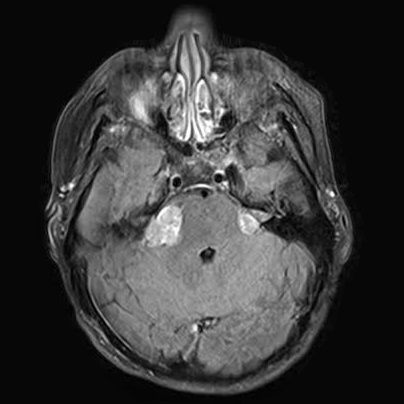

Upper Cranial

Meningioma

Upper Cranial Meningioma, tumor, MRI, scan

• Intracranial Meningioma: (54%)

Meningioma can easily develop throughout the brain

Meningioma develop as Encapsulated and Benign Tumors, as these tumors reach different sizes as a result of simple growth or treatment(s) of Radiation. Either way, Meningioma can have dangerous or even fatal consequences, depending on the World Health Organization (WHO). As a tumor grow the classification of the tumor may reach the next grade level and increased not just a tumors WHO grade, as well as speed of growth, but the chance that it will grow back if removed in surgery or may be hard to control with other treatments.[ Tew, 2013]

• WHO Grade 1: When these tumors start to grow they are slow growing, Benign.

• WHO Grade 2: These are Atypical tumors have a higher rate of regrowth if surgically removed.

• WHO Grade 3: These tumors are Malignant / Anaplastic, (irrespective of brain invasion).